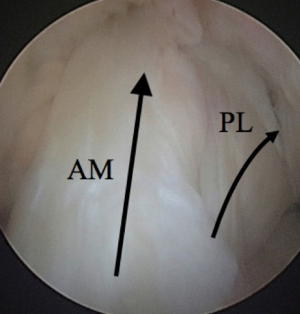

ACL injury may be the greatest contributor to knee instability and pain. The ACL originates at the intercondylar notch on the lateral femoral condyle and its insertion is on the tibial articular surface between the medial and lateral tibial spines. It functions to provide anteroposterior stability, as well as to control rotation of the knee. The ACL is made up of two bundles which are named for their tibial insertion site locations: the anteromedial (AM) and the posterolateral (PL) bundles (Figure 4). The AM bundle is tight in flexion while the PL bundle tightens with knee extension. Acute ACL injuries typically occur as a non-contact pivot type injury, and commonly one feels a “pop” and has immediate swelling and pain. This injury pattern is thought to occur when the knee is in valgus, internal rotation, and 20 degrees of flexion with eccentric quadriceps contraction (11).

Figure 4 Arthroscopic image of the anteromedial (AM) and posterolateral (PL) bundles of the ACL with arrows indicating their direction.